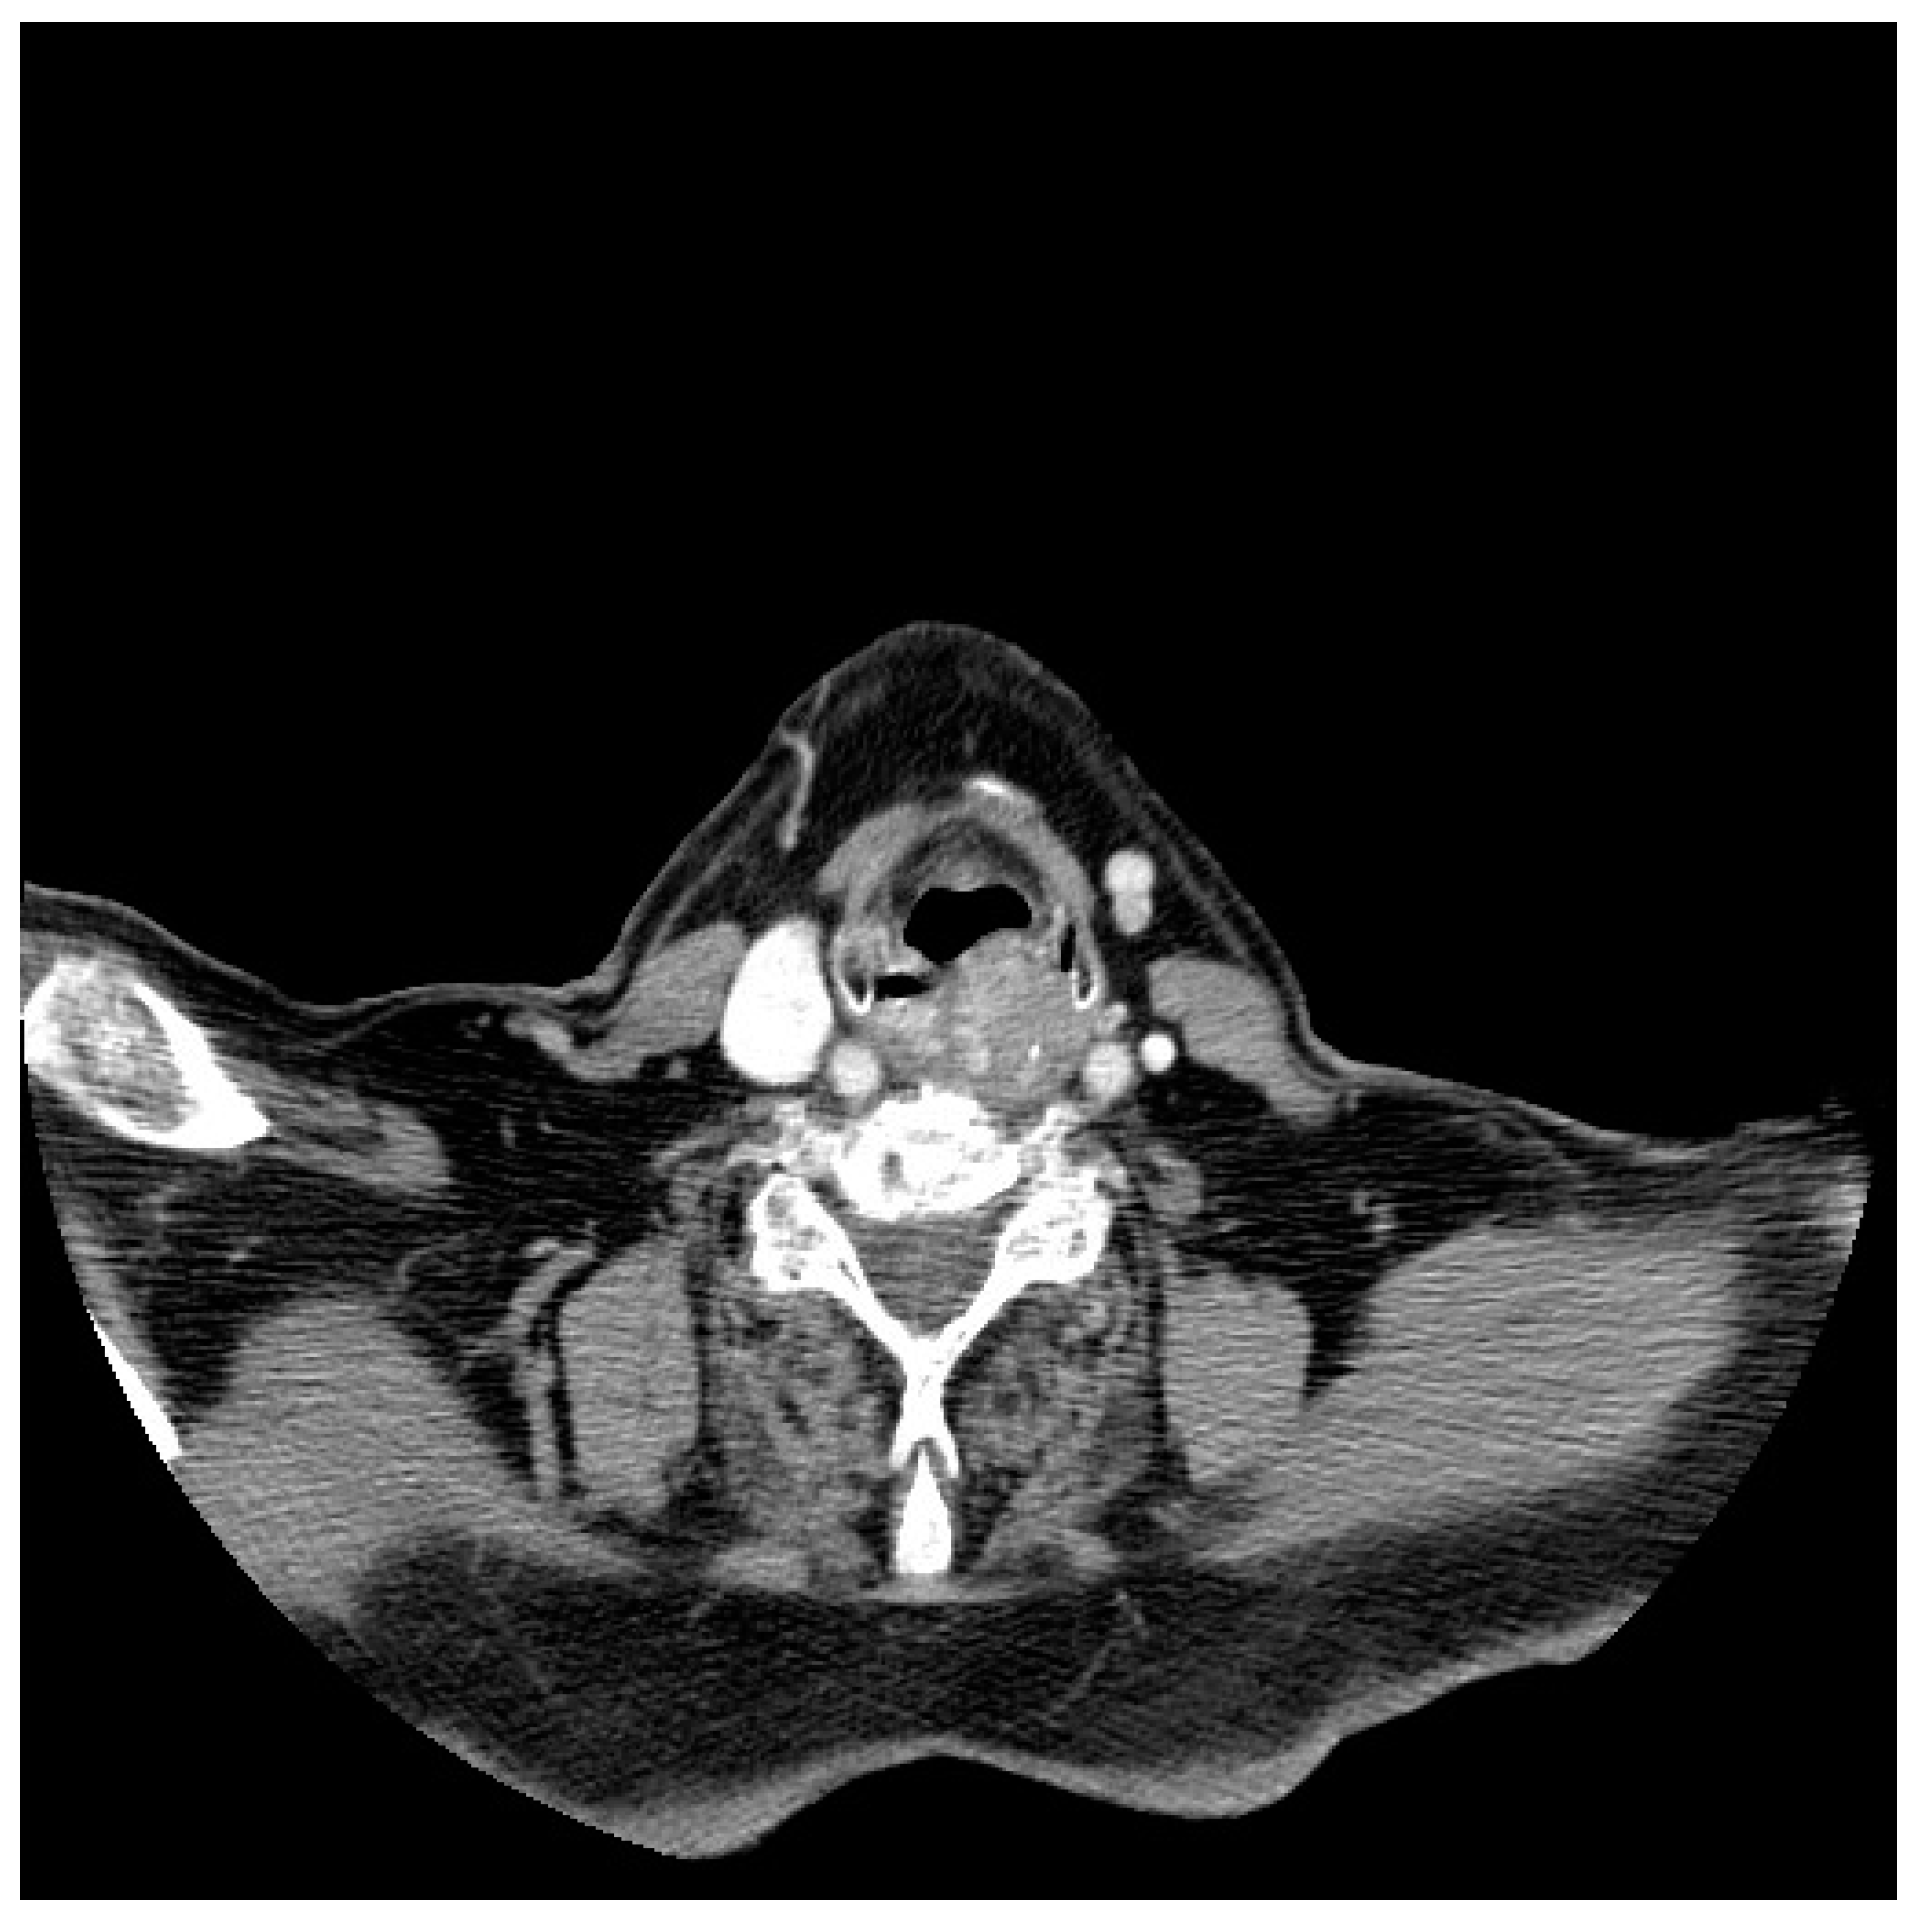

3.1. Diagnostic Workup

- Doğan, S.; Vural, A.; Kahriman, G.; İmamoğlu, H.; Abdülrezzak, U.; Öztürk, M. Non-squamous cell carcinoma diseases of the larynx: Clinical and imaging findings. Braz. J. Otorhinolaryngol. 2020, 86, 468–482. [Google Scholar] [CrossRef]